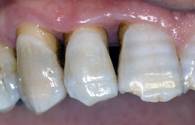

Fig 9

Clinical re-evaluation 10 days after surgery

Int J Med Sci Image

Fig 10

Clinical re-evaluation 6 months after surgery

The management of the soft tissues was easy and healing almost in a high rate occurred after the first treatment. During sutures removal, no important tissues inflammations were observed. At a 10-day follow-up, post-operative clinical assessment demonstrated a gingivitis grade of 0 or 1. Thanks to the bacteriostatic properties of the tested polymer, a more effective control of the surgical wound no bacterial contamination of the surgical site was observable in all instances [fig. 9]. Post-operative radiographs showed absence of bone remodelling, and satisfactory filling of the infra-bone defects with the graft material in situ. After 6 months, radiographs showed presence of mild bone remodelling and excellent infra-bone filling [fig. 10-11].